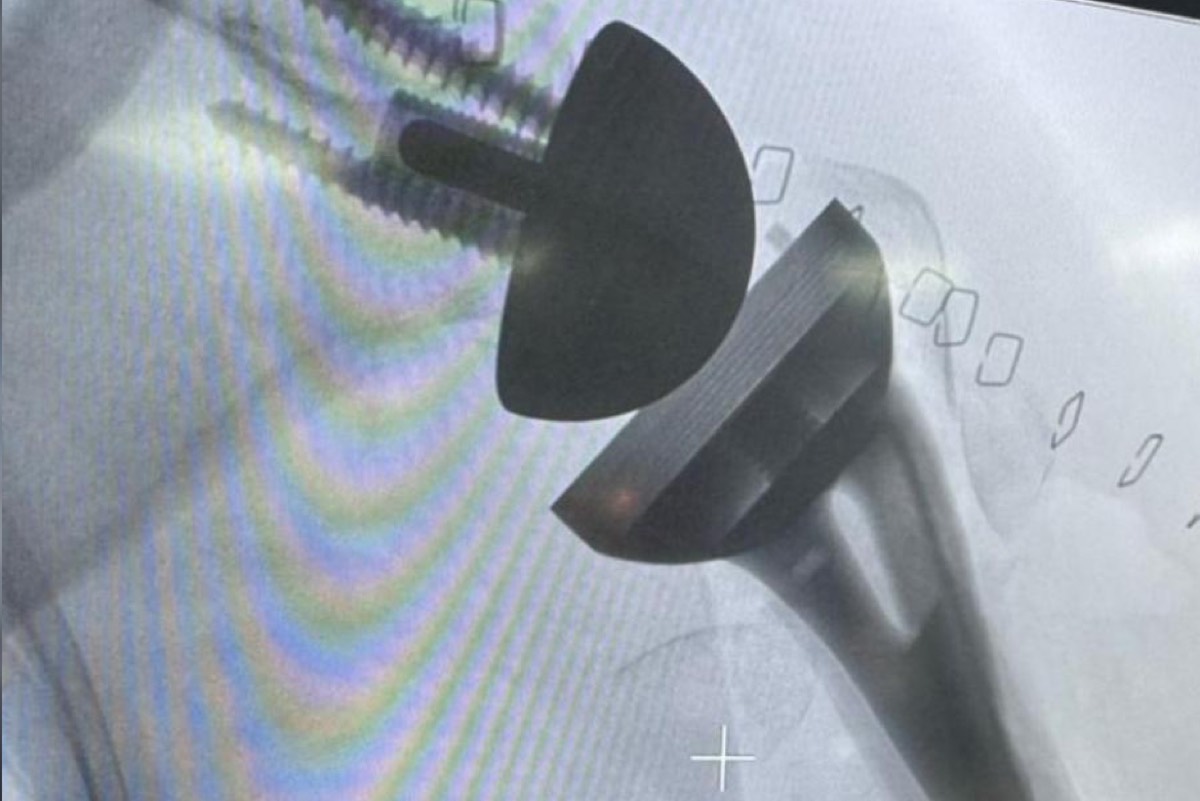

باشر قسم جراحة العظام بمستشفى القطيف المركزي، تقديم خدمات استبدال مفصل الكتف الكلي، في خطوة استراتيجية تُعد إنجازاً طبياً نوعياً يهدف إلى الارتقاء بمنظومة الخدمات الصحية التخصصية وتوطين الجراحات الدقيقة لخدمة أهالي المنطقة.

وتوج الفريق الطبي هذا التدشين بإجراء أول عمليتين جراحيتين من هذا النوع تكللتا بالنجاح التام، حيث تجاوزت المريضتان مرحلة العمليات وتخضعان حالياً لبرنامج تأهيلي طبي متكامل ومكثف تحت إشراف طواقم متخصصة لضمان استعادة الوظائف الحركية بكفاءة عالية.